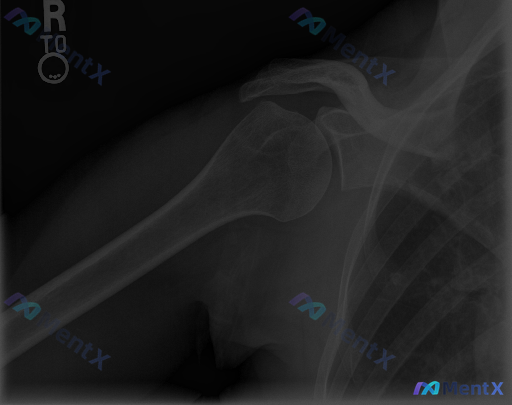

整理到一份右肩关节正位X光的影像资料,想和大家讨论一下读片思路。 核心影像表现: - 肱骨大结节区域:皮质密度增高、不规则骨赘形成、形态毛糙,骨小梁结构略显紊乱 - 肩锁关节:轻度间隙变窄、关节面骨质硬化 - 盂肱关节:对合良好,间隙无明显狭窄 - 其余:未见明确骨折、脱位,无明显钙化灶,无恶性骨肿...